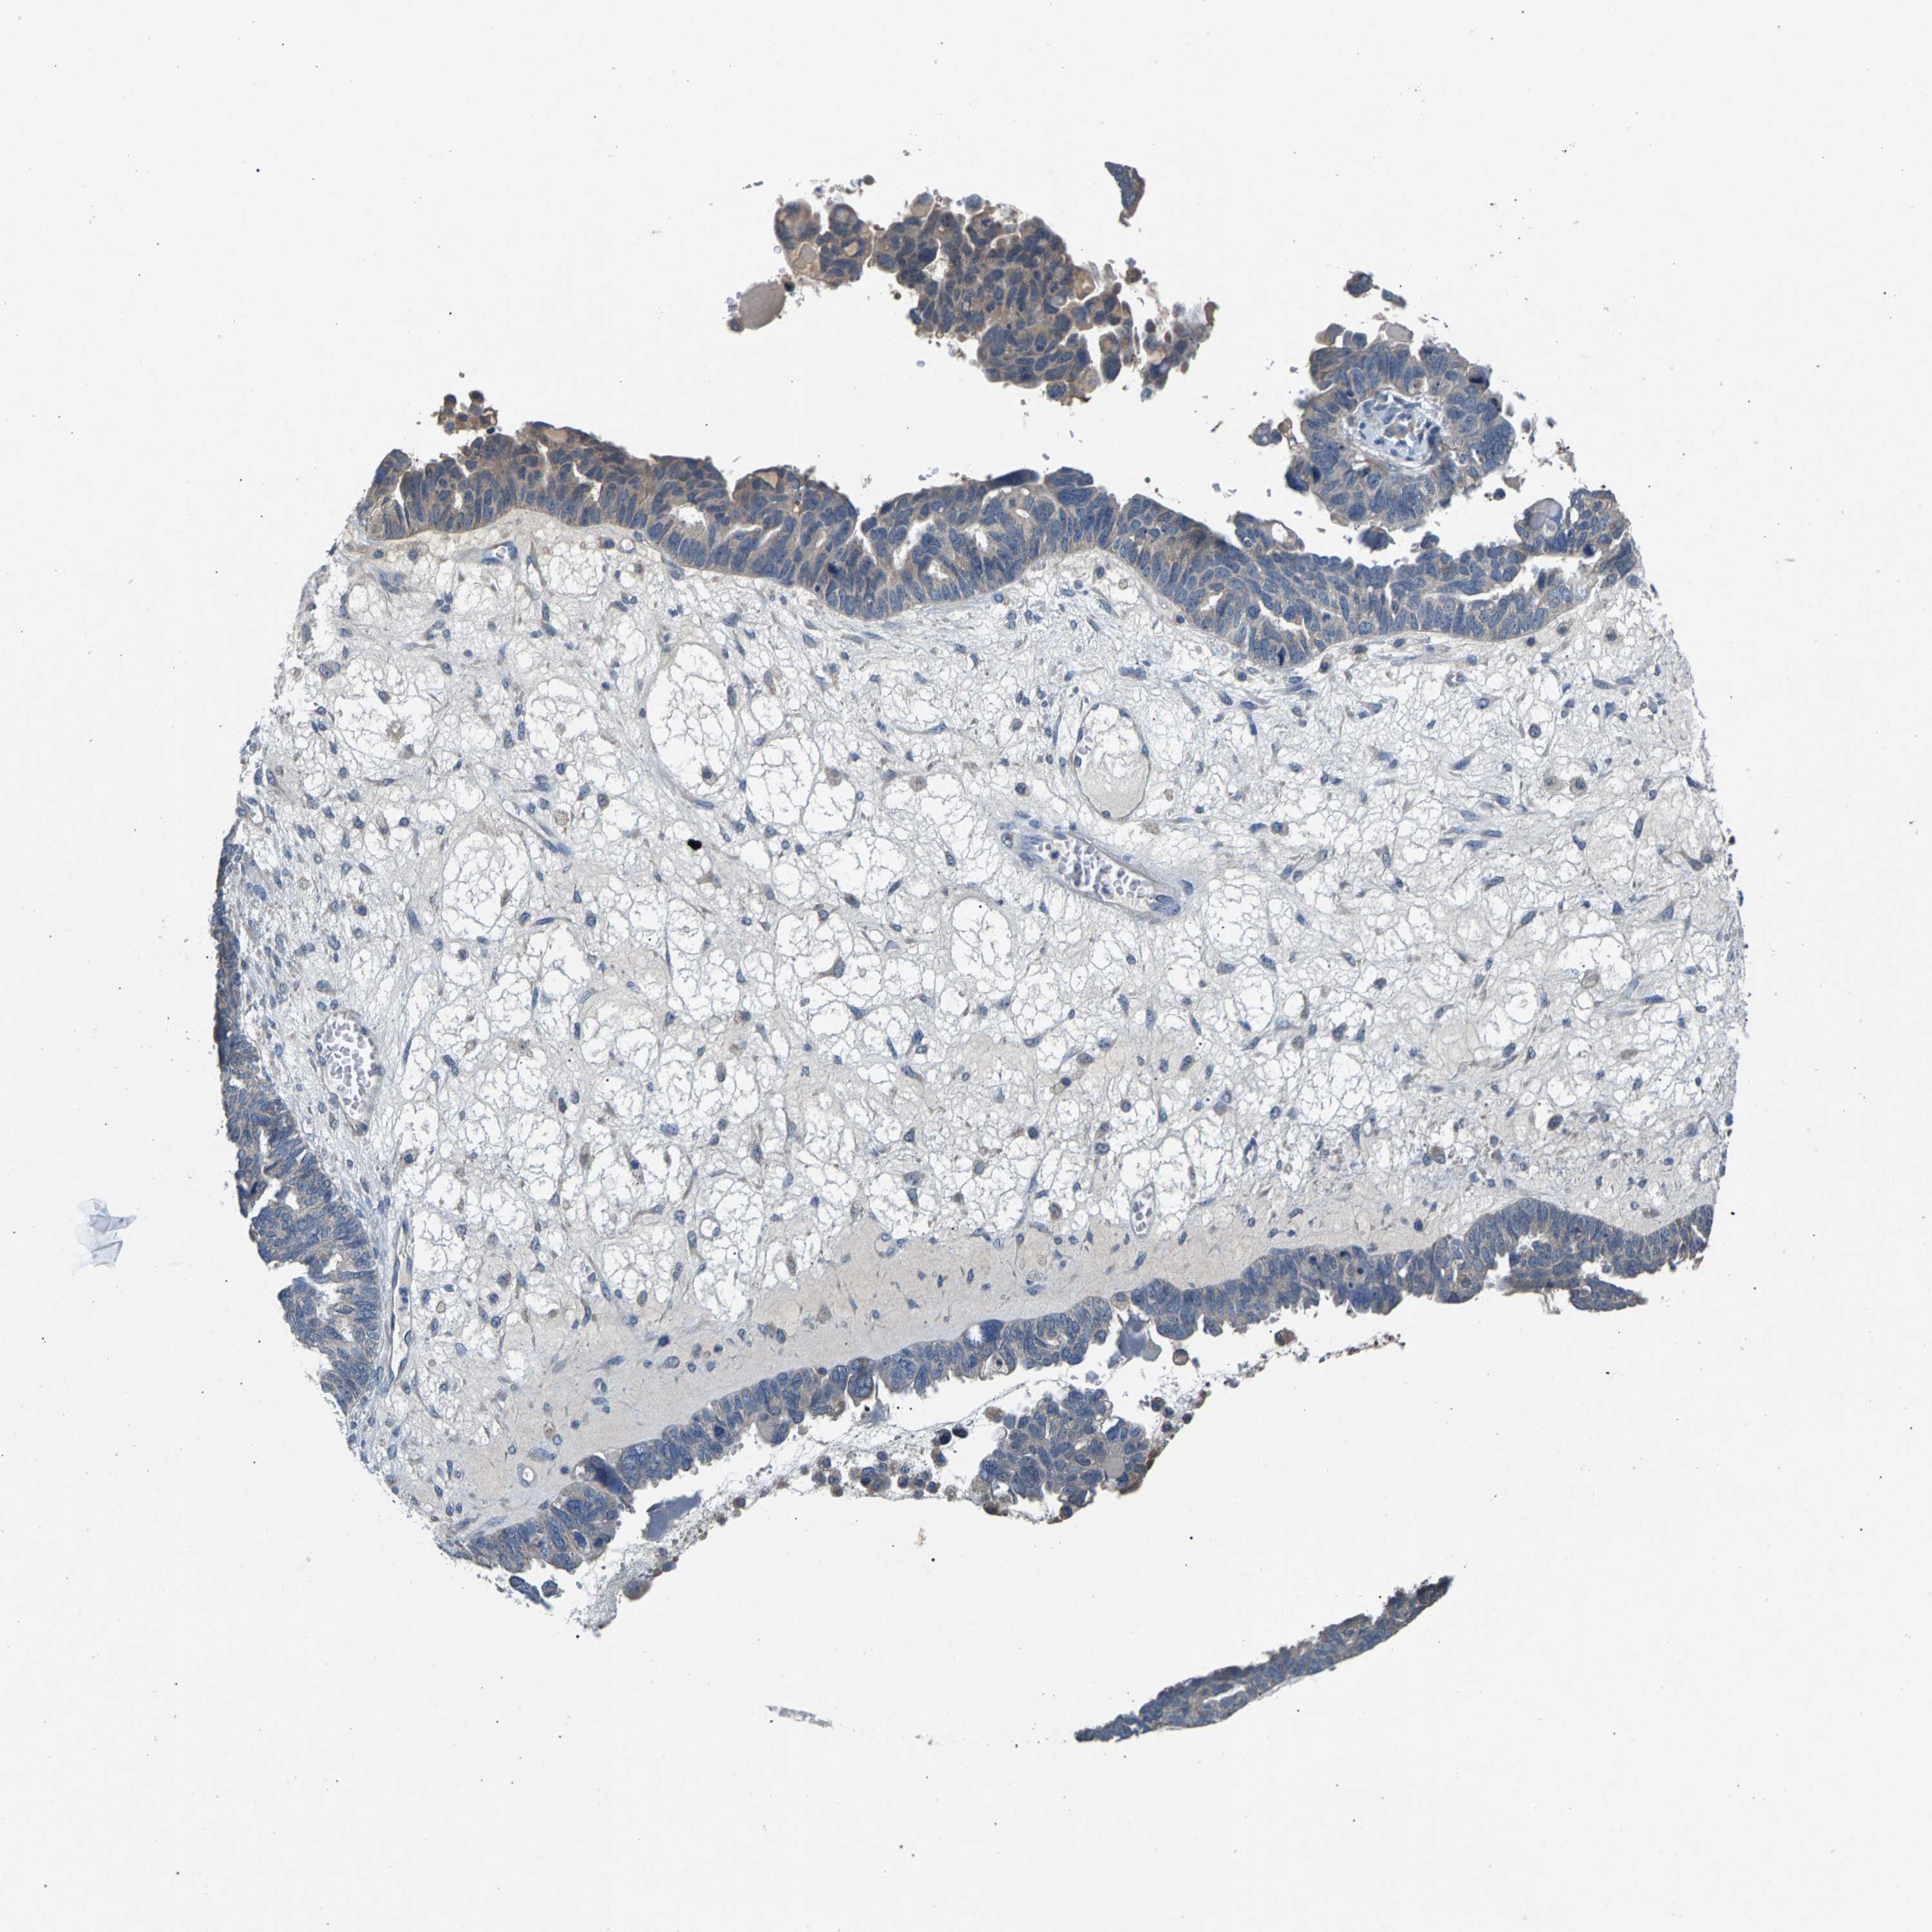

OVARIAN CANCER - Protein expressioni

A mouse-over function shows sample information and annotation data. Click on an image to view it in a full screen mode. Samples can be filtered based on level of antibody staining by selecting one or several of the following categories: high, medium, low and not detected. The assay and annotation is described here.

Note that samples used for immunohistochemistry by the Human Protein Atlas do not correspond to samples in the TCGA dataset.

Antibody stainingi

Antibody staining in the annotated cell types in the current human tissue is reported as not detected, low, medium, or high, based on conventional immunohistochemistry profiling in selected tissues. This score is based on the combination of the staining intensity and fraction of stained cells.

Each image is clickable and will lead to virtual microscopy that enables deeper exploration of all samples and also displays staining intensity scores, fraction scores and subcellular localization as well as patient and tissue information for each sample.

Antibody HPA021581

Antibody HPA023632

Staining

High

Medium

Low

Not detected

Intensity

Strong

Moderate

Weak

Negative

Quantity

>75%

75%-25%

<25%

None

Location

Nuclear

Cytoplasmic/membranous

Cytoplasmic/membranous,nuclear

Cystadenocarcinoma, serous, NOS

Carcinoma, endometroid

Cystadenocarcinoma, mucinous, NOS

Carcinoma, NOS